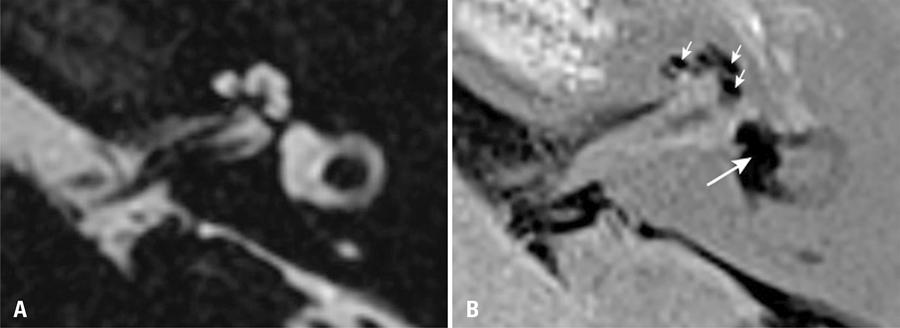

Figura 1

Imagens de ressonância magnética no plano axial do ouvido esquerdo de paciente diagnosticado com doença de Ménière. (A) Sequência altamente ponderada em T2 mostra o espaço dos fluidos labirínticos (soma dos espaços endolinfático e perilinfático). (B) Sequência inversion recovery turbo spin echo with real reconstruction (3D real-IR) 4 horas após administração intravenosa de gadolínio mostra distensão do sáculo e utrículo, que ocupam a maior parte da área vestibular (seta grande), e a distensão significativa do ducto coclear (setas pequenas)